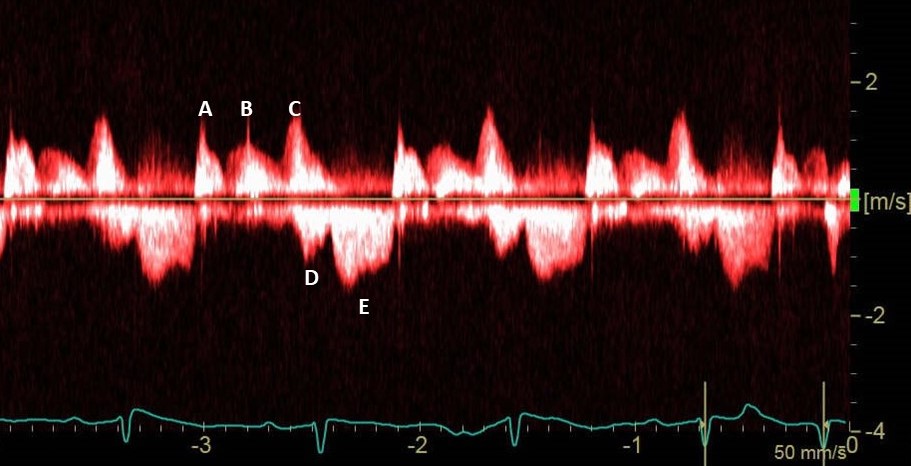

Kamel Chair Ritu Thamman MD Lukasz Zydzik Dr G Rajesh (Gopalan Nair Rajesh). Edgar Argulian Dr Jason Dungu PhD FRCP FESC Tuğba Kemaloğlu Öz, A/Prof Dr. Purvi Parwani Nicolas Merke Brian Wood Fresh thrombi may have hypoechoic core. Hier is a case of fresh thombi, all gone after effective oral anticoagulation within 1 week